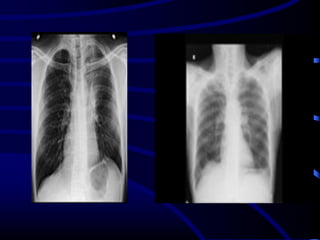

Usual Interstitial Pneumonia UIP

HRCT Findings

Reticular opacities, thickened intra- and

interlobular septa

Irregular interfaces

Honey combing and parenchymal distorsion

Ground glass opacities (never prominent)

Basal and subpleural predominance

Basal and subpleural distribution

UIP

Honeycombing and traction bronchiectasis in UIP.

Typical UIP with honeycombing and traction

bronchiectasis in a patient with idiopathic

pulmonary fibrosis (IPF)